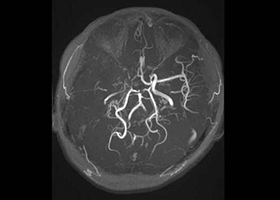

③ もやもや病に対する頭蓋内外脳血行再建術

もやもや病は原因不明の進行性脳内血管狭窄疾患であり、国によって難病指定されている病気です。典型的には小児や若年成人に起こり、脳虚血(脳梗塞)、脳出血を生じます。頭蓋内外脳血行再建術(バイパス手術)が必要な場合があります。

38歳、もやもや病、左半身一過性脳虚血発作

[画像所見]

-

右 頭部MRI -

頭部MRA(脳血管の脱落、赤丸部) 左

[術後画像検査]

術前MRA -

術後MRA

術後はバイパス血管が脳内に向かって出現しています(赤丸印)。